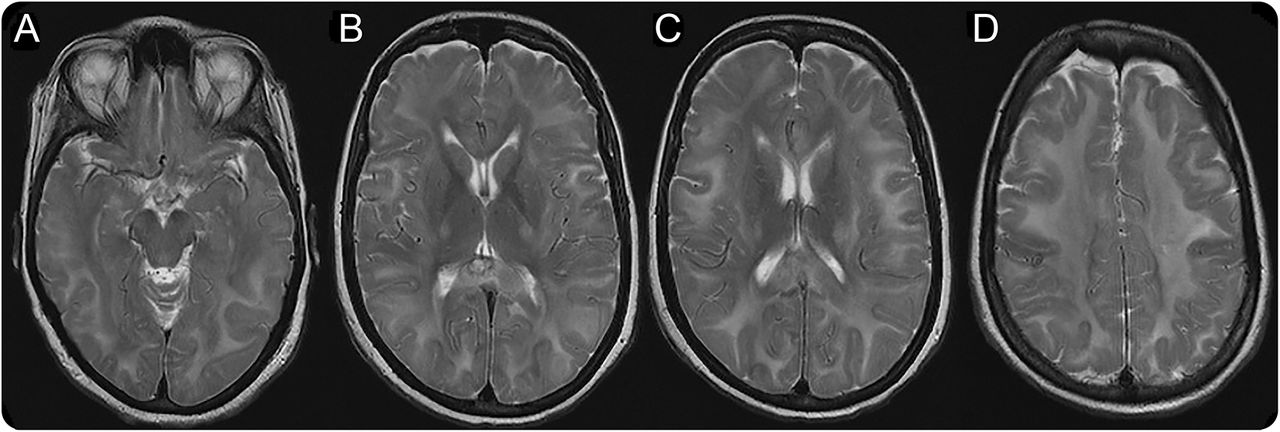

神经影像学研究结果缺乏硫胺转运体

神经影像学研究SLC19A3基因突变。(模拟)轴向大脑MRI披露明显扩散hyperintensity深远的和大脑皮层下白质和皮质脊髓束hyperintensity内囊后肢的t2加权图像。